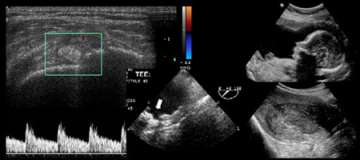

Ultrasound is a popular, cost-effective imaging tool. High frequency sound waves travel from the ultrasound probe through human tissue. Some of the sound waves bounce back to the transducer. This reflected sound is used by a computer to form the ultrasound image. There is no radiation dose associated with the ultrasound scan.

Ultrasound is the examination of choice in obstetrics. It is used to determine the age, level of development of the fetus and the presence of birth defects or other potential problems.

It is also the examination of choice in young women with pelvic pain and in patients with suspected gallbladder problems.

Ultrasound is useful to study blood flow in larger arteries. It is commonly used to search for abnormal narrowing of the carotid arteries and to monitor aneurysms of the abdominal aorta.